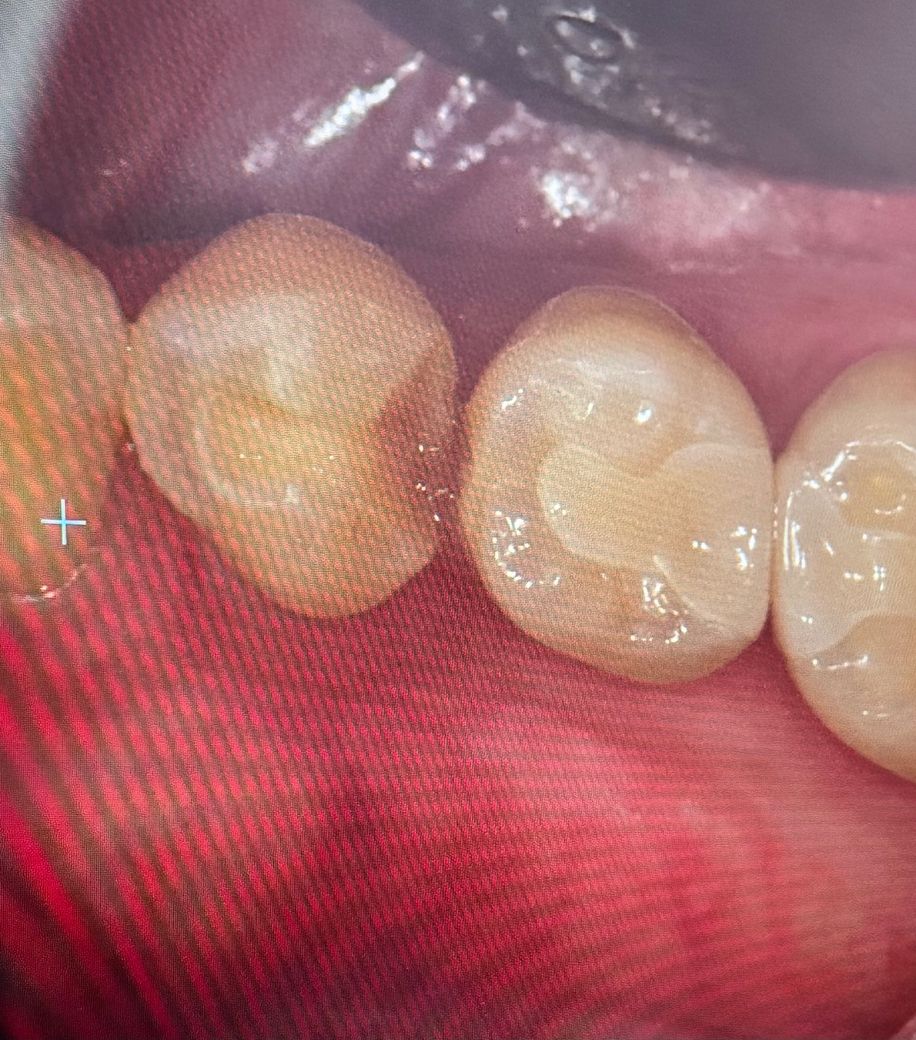

크라운 치료했는데 맞나봐주세요ㅠㅠ

사진상 왼쪽 치아에 때워둔게 떨어져서 치과에 갔어요(사진 상 깨져보이는 치아)

근데 그 옆 치아에 충치가있다고 크라운을 씌워야한다하셔서, 인레이로 진행하고싶었는데 안 된다고해서 ㅜㅠ크라운치료 이미 진행중이에요ㅠㅠ

충치가 심해보이지도않고(의사는 심하다고함)

, 치아는 삭제하면 다시 못 돌리는데..다른병원 가봤어야하나 후회가 돼서요

다른전문가분들이 보기엔 저 치아에 크라운이 맞나요? 인레이로는 안 되나요? 의사선생님이 말 하길 인레이는 사이에 틈이생기면 다시 충치가 생길수있고 너무 넓게 붙이면 치아가 부서질수 있다고하셨어요.. 이사하고 처음가본 치과라 혹시 과잉진료가 아니었는지 궁금해서요

• 1번 째 사진

엑스레이를 확인해보고 옆면에 충치가 잇다면 크라운 치료를 하셔도 크게 무방한 치아엿을것같습니다.

일반적으로 mod 인레이 형태 (양옆이 연결된 형태) 는 비추천합니다 금방파절되고, 쐐기효과로 치아도 부러뜨릴 수 있습니다